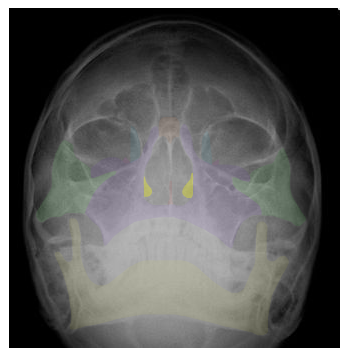

in yellow,  | ETHMOID |

| SPHENOID |